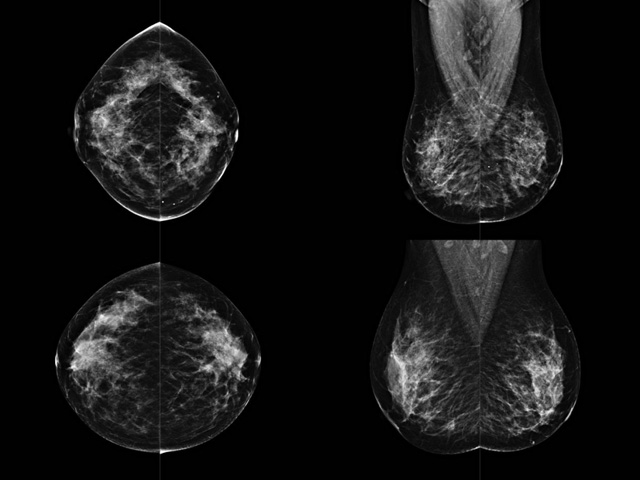

乳腺DR成像設(shè)備中非晶硅跟非晶硒兩種平板探測(cè)器

乳腺DR成像設(shè)備中非晶硅跟非晶硒兩種平板探測(cè)器。更要提供優(yōu)質(zhì)的圖像質(zhì)量乳腺的組織結(jié)構(gòu)與厚度各不相同,減少重拍率輻射劑量,,乳腺的主要構(gòu)成組織均為軟組織結(jié)構(gòu),組織之間密度十分相似,缺乏天然對(duì)比度。選擇軟X線攝影技術(shù)獲得良好對(duì)比度的乳腺結(jié)構(gòu)影像。增加各組織對(duì)X線的吸收差異。乳腺攝影測(cè)和分類(lèi),平板探測(cè)器的像素尺寸范圍應(yīng)在50到100μm之間。特別是微鈣化灶可以小到100到200μm,平板探測(cè)器都必極小微鈣化灶進(jìn)行成像。

乳腺DR是利用X光來(lái)做檢查,在一瞬間將被檢測(cè)到的位置投影出來(lái),因?yàn)槭撬查g的輻射,所以只需要0.5秒的時(shí)間。因此對(duì)病人的輻射很低,大約是0.023mSv,比國(guó)家的標(biāo)準(zhǔn)要低得多。DR系統(tǒng)由 X線、發(fā)生裝置、直接轉(zhuǎn)換平板探測(cè)器、系統(tǒng)控制器、影像監(jiān)視器、影像處理工作站等組成。能檢查胸腔積液、肺結(jié)核、大葉性肺炎、肋骨骨折等。心室增大、主動(dòng)脈擴(kuò)張、主動(dòng)脈瘤等心臟病。腹部病變,如腸梗阻、腸穿孔等,DR上可見(jiàn)液氣平面、膈下游離氣腫。DR表現(xiàn)不正常,要結(jié)合臨床表現(xiàn)、體征、癥狀等綜合分析,結(jié)合CT、彩超、血液分析等,才能作出正確的判斷。